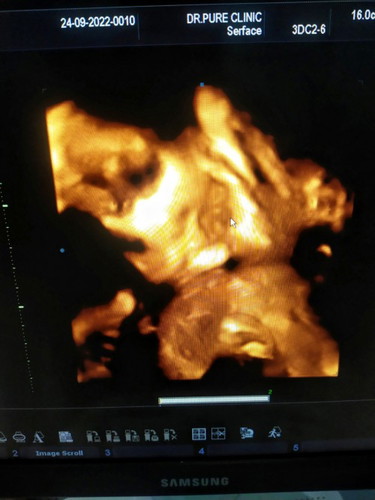

25+6 สัปดาห์ 900 กรัม

ป้าหมอบอกน้องตัวใหญ่น่ะแม่ กินเบาๆหน่อย ลดขนมด่วนเลย จากนี้ไปแม่จะไม่กินจุกจิกแล้ว